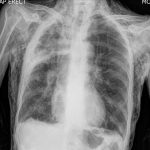

Gãy xương sườn là một tổn thương thường gặp trong chấn thương lồng ngực. Gãy trực tiếp: tác nhân gây chấn thương ở đâu thì xương sườn gãy ở đó. Đây là loại gãy từ ngoài vào, do đó tạng nào nằm ngay sát ổ gãy dễ bị thương tổn nhất (thường là phổi). Gãy gián tiếp: tác nhân gây chấn thương ép từ phía trước ngực, còn phía sau lưng là một vật cản cố định, lồng ngực bị ép dẹt lại theo chiều trước sau, cung bên của xương sườn sẽ bị gãy. Tạng nằm giữa trung thất là tạng dễ bị thương tổn (tim, mạch máu lớn)…

Gãy xương ức ít gặp trong chấn thương ngực. Nguyên nhân thường do lực tác động mạnh trực tiếp lên mặt trước của xương ức hoặc do chấn thương làm gập mạnh xương ức lại (như trong trường hợp gãy lún đốt sống). Hầu hết các trường hợp đường gãy thường nằm ngang và hay gãy tại chỗ sụn tiếp giáp giữa cán ức và thân ức…